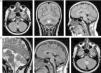

Valorado por neurocirugía, se decide mantener actitud expectante respecto a la lesión cerebelosa y se realizan controles seriados en neurocirugía y neurología, incluyendo RMC anual. Se prueba tratamiento con metilfenidato y atomoxetina, con escasa respuesta. A los 5años del diagnóstico persisten problemas de aprendizaje, con dificultades en lectura y en comprensión lectora, dificultades para el razonamiento lógico abstracto matemático, problemas de coordinación motriz y de psicomotricidad, y motilidad fina y dificultades para la orientación de líneas y el dibujo geométrico. Así mismo, persisten problemas de interacción social recíproca, es un niño introvertido con inmadurez social, dificultad para comprender el sentido de las bromas, baja autoestima y sentido de incapacidad ante los problemas cotidianos. La lesión cerebelosa ha permanecido estable, con muy discreto crecimiento. En la figura 2 se muestran las imágenes de RM cerebral al diagnóstico y a los 5años de seguimiento.

Resonancia magnética cerebral al diagnóstico y tras 5años de seguimiento que muestra lesión expansiva de localización extraaxial, caudal al vermis cerebeloso, hipotensa en T1 e hiperintensa en T2, sin edema perilesional, efecto masa ni captación de contraste. A)RM cerebral al diagnóstico (axial FLAIR tras gadolinio, coronal T2, sagital T1). B)RM cerebral de control tras 5años de evolución (sagital T2, sagital T1, axial FLAIR tras gadolinio).